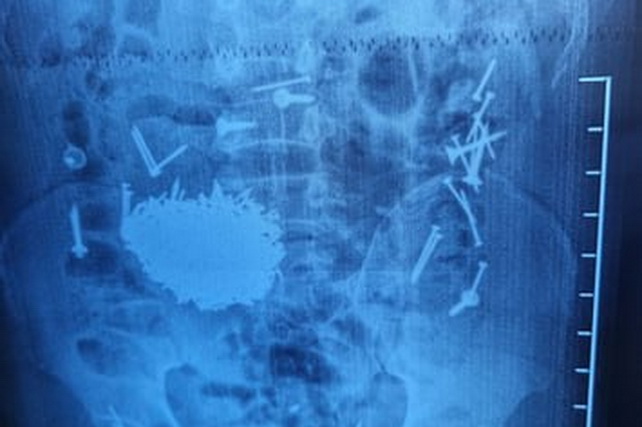

Diagnostic examinations and laboratory tests revealed a large number of metallic objects — nails and screws — in the patient’s gastrointestinal tract.

The patient underwent surgical intervention using laparotomy and gastrostomy techniques. Approximately 200 grams of metal objects were successfully removed from his abdominal cavity.